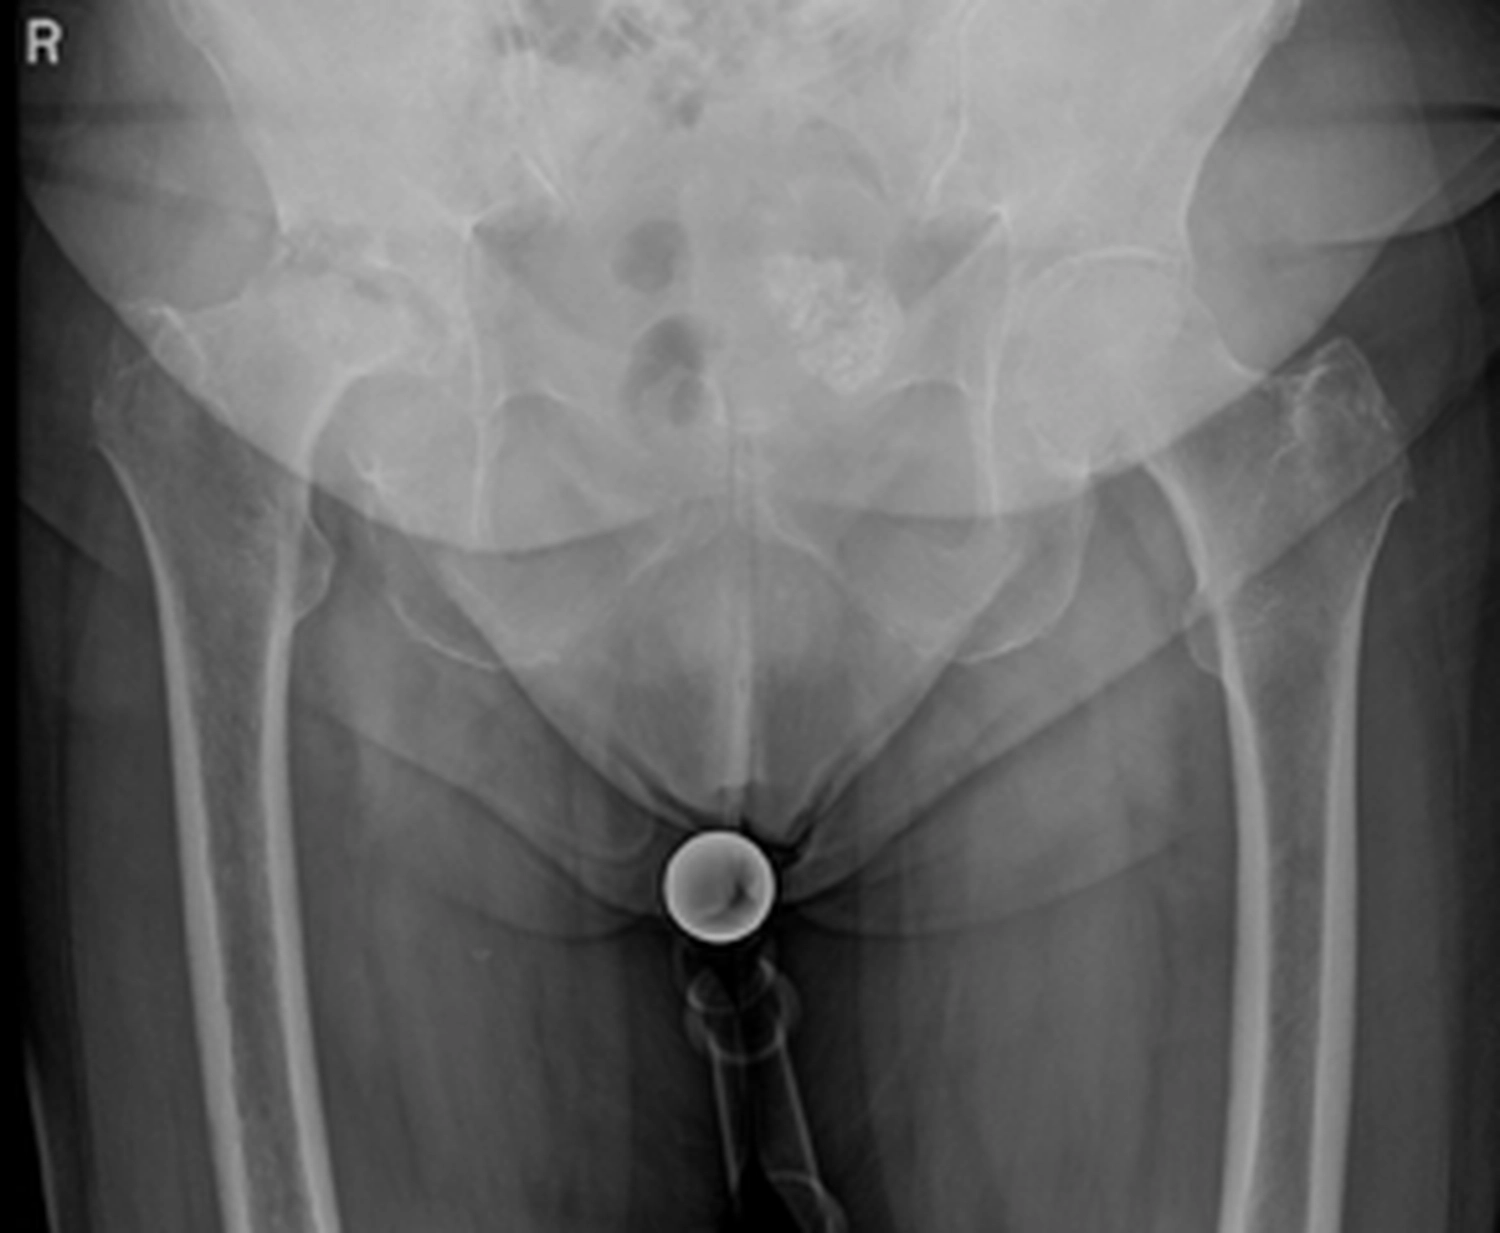

Ein künstliches Hüftgelenk ersetzt die geschädigten Teile des natürlichen Gelenkes. Es besteht aus mehreren Komponenten, die gemeinsam ein neues, stabiles und bewegliches Gelenk bilden. Die Pfanne wird in das Becken eingesetzt. Der Schaft wird im Oberschenkelknochen verankert. Der Prothesenkopf sitzt oben auf dem Schaft und bildet die „Kugel“ des Gelenkes und bewegt sich reibungsarm in der Pfanne.

Je nach Knochenqualität und Alter der PatientInnen werden zwei Verfahren angewendet.

Bei der zementfreien Prothese werden der Schaft und die Pfanne fest eingepresst und eingeschlagen. Der Knochen wächst in die aufgeraute Oberfläche ein und fixiert die Prothese dauerhaft.

Bei der zementierten Prothese werden die Prothesenteile mit einem speziellen Knochenzement befestigt. Der Vorteil besteht in einer sofortigen Stabilität, besonders geeignet bei älteren oder osteoporotischen PatientInnen.

Daneben gibt es sog. Hybridverankerungen, z. B. Pfanne zementfrei, Schaft zementiert.